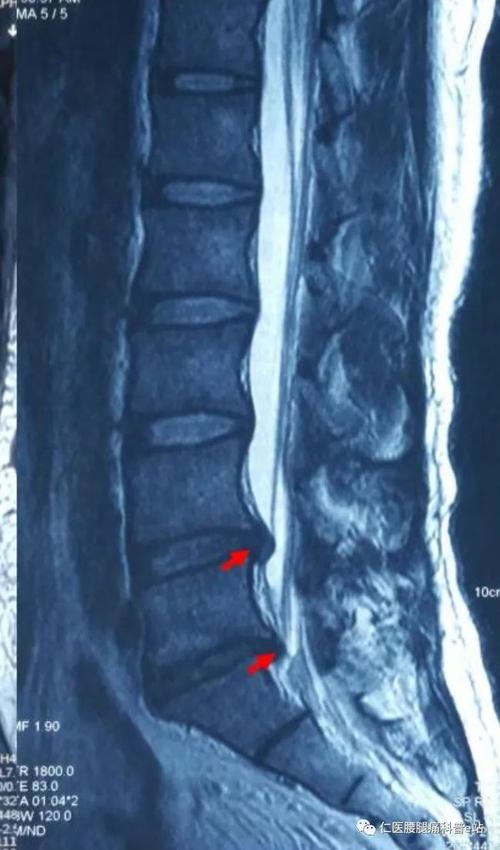

腰椎核磁共振图片讲解,新手看腰椎MRI片图解

患者陈先生腰椎mri片(核磁共振成像)

核磁共振示腰5骶1间盘突出

新手看腰椎MRI片图解

新手看腰椎核磁图解

腰椎核磁共振片子图解

腰椎核磁共振讲解

腰椎间盘突出核磁共振